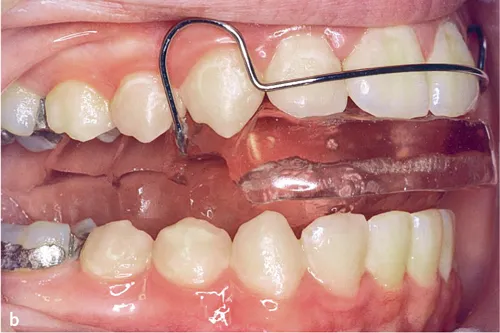

Abb. 3a bis c Intraorale Fotos von drei Aktivator-Patienten mit unterschiedlich hohen Konstruktionsbissen: a) Niedriger Konstruktionsbiss (2–4 mm)1, b) hoher Konstruktionsbiss (15–20 mm)10 und c) mittelhoher Konstruktionsbiss (5–7 mm)11.

2.Bei einem sehr hohen Konstruktionsbiss (15–20 mm), weit außerhalb der Unterkiefer-Ruheschwebelage (Abb. 3b), wird die tonische Spannung der gestreckten Muskulatur erhöht und kontinuierliche Kräfte wirken auf die Zähne10. Der Aktivator ist wie ein Splint zwischen die Zahnreihen eingeklemmt. Der sehr hohe Konstruktionsbiss wird vor allem in Amerika verwendet.